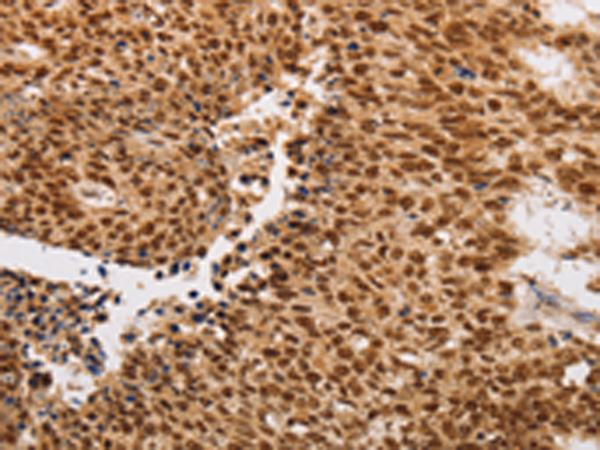

分类: 科研抗体货号: P08022别名: LK4; hCERK; dA59H18.2; dA59H18.3应用: IHC反应种属: Human, Mouse